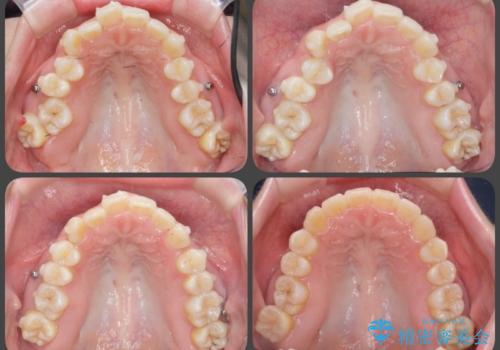

[ インビザライン ] 目立たないマウスピース矯正で、前歯のがたつきをきれいにしたい

- 前歯のがたつきを「装置の目立つワイヤーではなく、マウスピースで治療したい。」と希望され来院されました。

シミュレーションを作成した結果、26枚以下のリーズナブルなモデレートプランが適応であることがわかりました。

軽度ながたつきの場合、費用を抑えたプランでマウスピース矯正治療を行うことができる場合がありますのでぜひご相談ください。

費用を抑えられただけでなく、治療期間も約半年と短期間で治療を終了することができました。